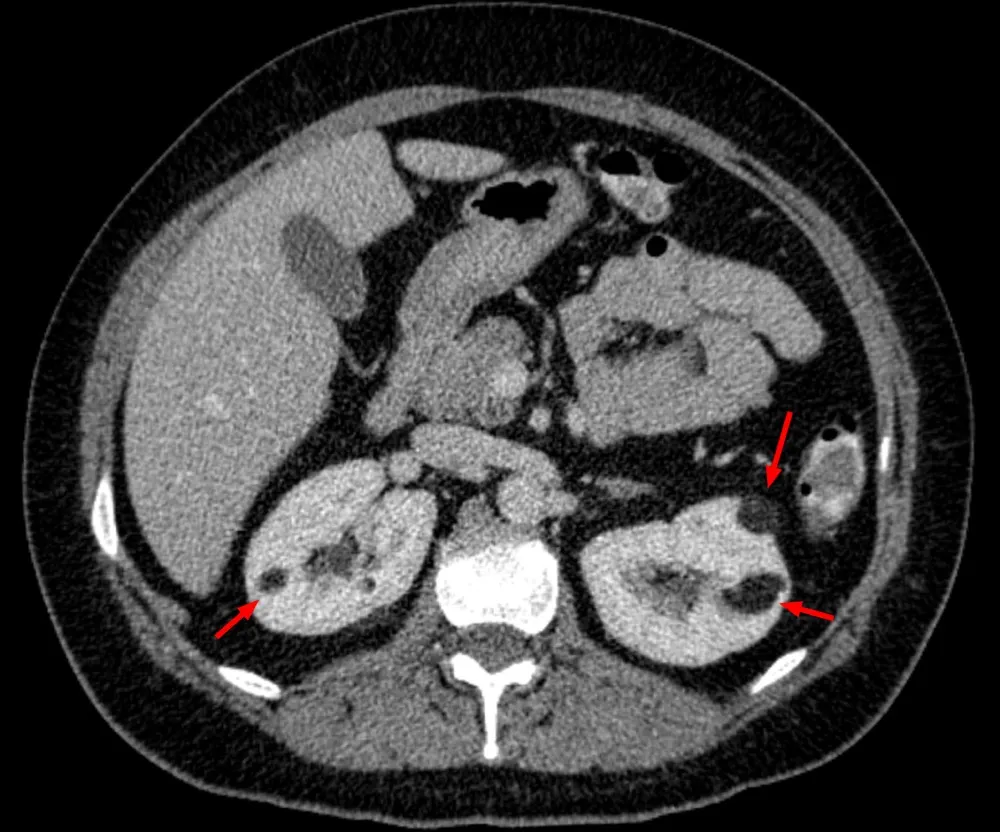

Paciente dislipidêmica, 47 anos, tomando suplemento "natural" para colesterol. Nenhuma queixa renal — até a creatinina chegar em 4.26. O agente não era uma droga controlada. Era arroz vermelho fermentado. E o rim foi o alvo.